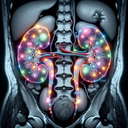

МРТ нирок

МРТ нирок — це неінвазивне обстеження, яке використовує магнітне поле і радіохвилі для отримання детальних зображень нирок. Воно допомагає діагностувати різноманітні захворювання, такі як пухлини, камені, інфекції чи вроджені вади. **Переваги МРТ:** 1...